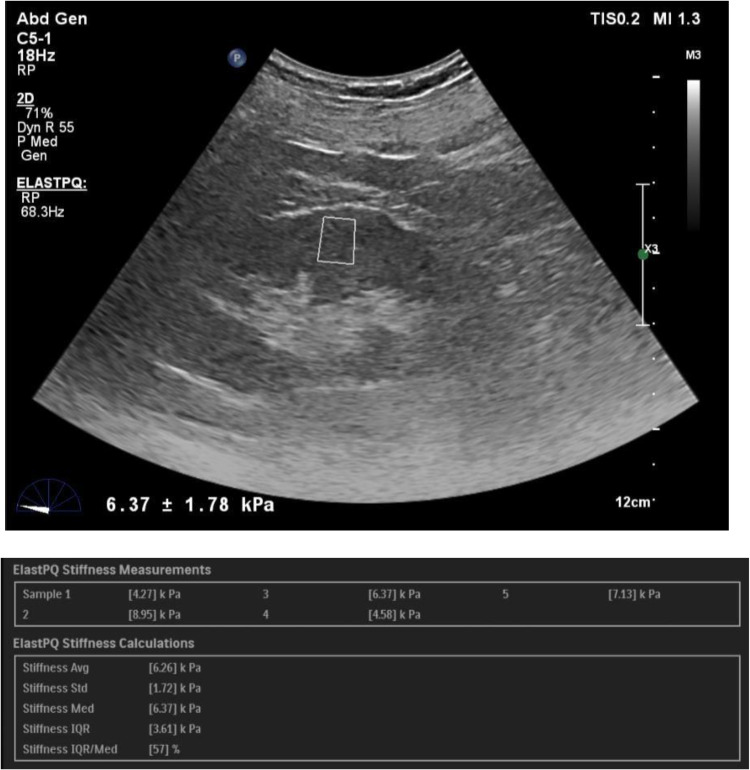

Materials and methods: The study protocol was approved by the Institutional ethics Committee at Kasturba medical college, Manipal and written informed consent was obtained from all participants. The study included 93 control subjects and 108 patients with CKD. SWE imaging was performed to assess renal cortical stiffness, as measured by the Young's modulus (YM). Correlations between SWE and conventional ultrasound parameters with age, serum creatinine, eGFR and serum urea were analysed using Pearson's correlation coefficient (p ≤ 0.05) and receiver operating characteristic (ROC) curves were derived.

Results: The diagnostic performance of SWE correlated with serum creatinine levels and eGFR. We found a statistically significant difference in kidney stiffness values between healthy individuals and CKD patients. The Spearman correlation coefficient revealed moderate negative linear correlation between the YM measurements and eGFR. We obtained a YM measurement cut-off value of 4.43 kPa, a value less than or equal to this suggested a no diseased kidney. This yielded sensitivity and specificity of 92.6% and 80.6%, respectively, with an AUROC of 0.92.